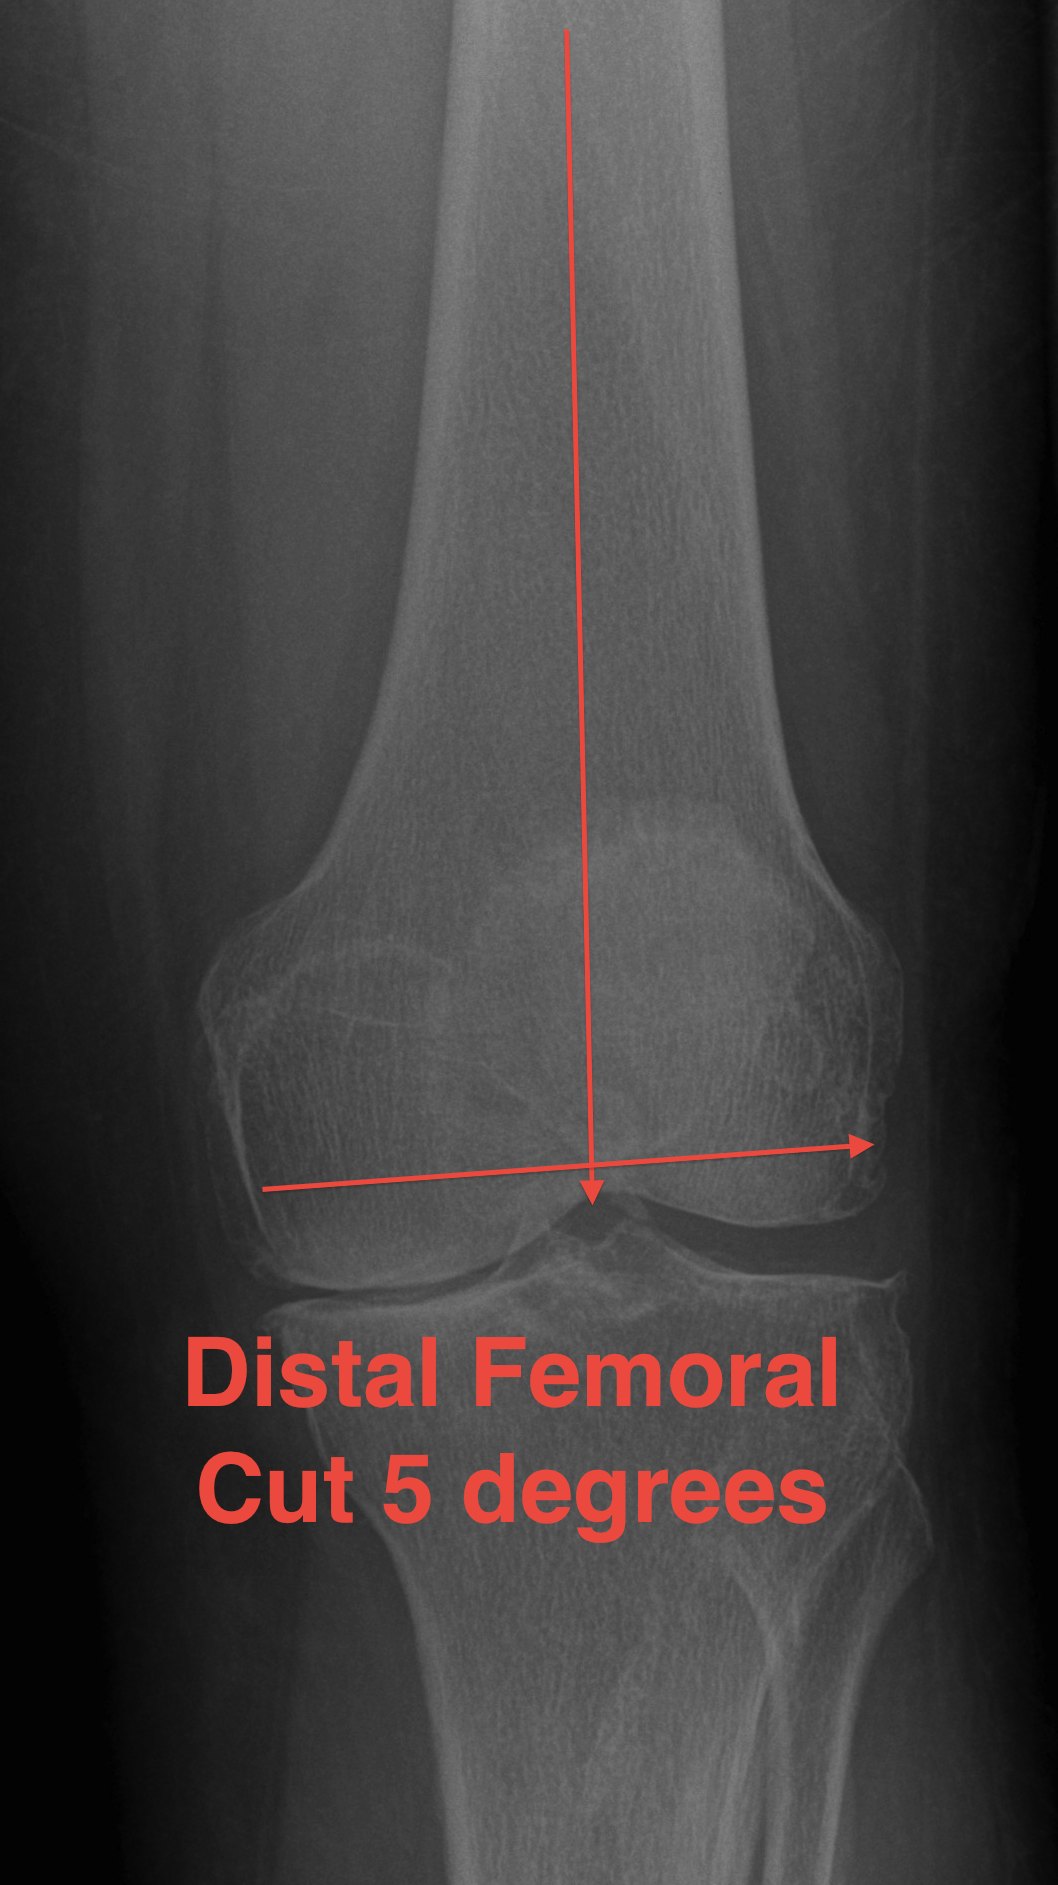

Distal Femoral Resection

Theory

- the tibia is cut at 0o

- want residual tibiofemoral axis to be 3-7o

- therefore, instead of cutting femur at 7-9o valgus, cut at 5-7o

- matched malalignment

Lateral plane

- at right angles to anatomic axis

Alignment

A. Intra-medullary best

B. Extramedullary less accurate

C. Significant deformity of femur / THR

- may need to use EM / short IM / computer navigation

Entry point

Clear osteophytes from intercondylar notch

Point

- 7 - 10 mm anterior to ACL

- slightly medial

- palpate femoral shaft

- pass IM drill reamer

- enlarge the hole to vent fatty contents

A. If entry too posterior

- will flex the femoral component and limit extension

B. If entry too lateral

- distal cut will be made in excessive valgus

Place IM rod & distal femoral cutting Jig

Valgus angle

- pre-op valgus cut angle

- 0o to mechanical axis

- 5 - 7o from anatomical axis

- usually 5o tall and thin, 7o short and fat